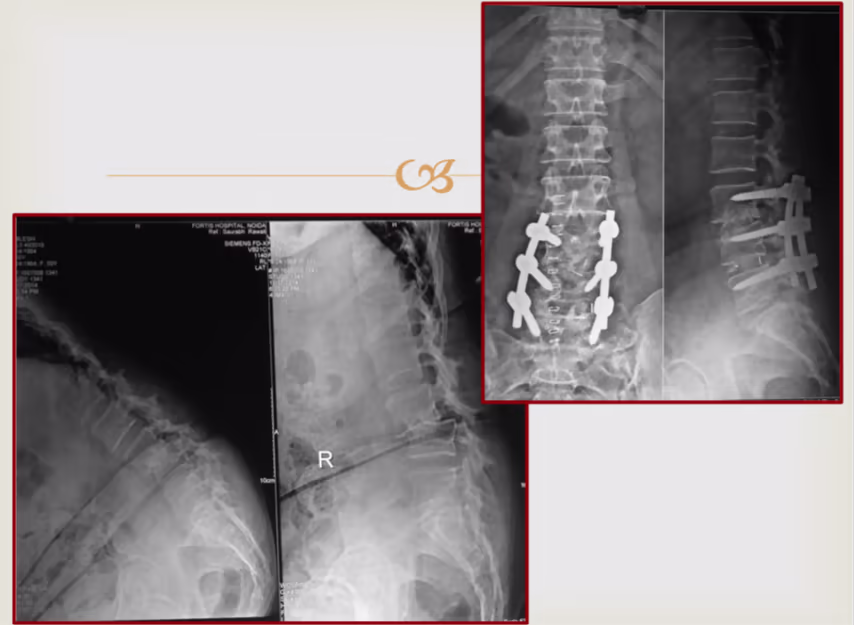

How is Spondylolisthesis Surgery done?

This operation is done from the back. In this operation, titanium screws are inserted in 2 spinal bones and the disc between them is taken out in entirety while protecting the spinal nerves. Then, a plastic cage filled with bone graft is packed in the place of the disc so that over a period of time, bone grows between the two bones and they become fused (joined) to each other. This eliminates any further risk of slipping and relieves the patient’s pain.